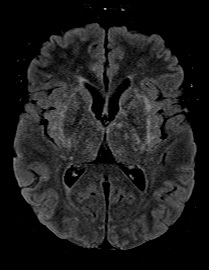

Results: A 38-year-old male developed tremors affecting the head and bilateral upper extremities two weeks after initiating escitalopram for anxiety. Head tremor had oscillations in vertical and horizontal planes. Upper extremities had Holmes tremor[4]–[6], 3–5 Hz in frequency, low-amplitude, seen at rest and action. Tremors persisted despite discontinuation of escitalopram. Magnetic Resonance Imaging showed extensive patchy, confluent T2 FLAIR signal abnormality involving bilateral basal ganglia, midbrain, and bilateral medial temporal lobes with punctate foci extending superiorly into the corona radiata, without gadolinium enhancement. This was stable on serial imaging. Cerebrospinal fluid (CSF) analysis showed oligoclonal bands and lymphocytic pleocytosis. Infectious, autoimmune, and paraneoplastic panels (serum and CSF) were negative except for minimally elevated Glutamic Acid Decarboxylase (GAD-65) antibodies in serum only. A PET scan identified increased uptake in left thyroid lobe, and histopathology from thyroidectomy confirmed papillary thyroid carcinoma. With imaging and serological workup suggesting paraneoplastic/autoimmune rhombencephalitis, immunotherapy with pulse steroids and plasma exchange was initiated without significant benefit. Intravenous immunoglobulin and cyclophosphamide provided limited neurological improvement. Tremors were refractory to multiple medication trials: head tremor responded to botulinum toxin injections, and trihexyphenidyl modestly improved upper extremity tremors. Over the next two years, he developed pseudobulbar affect and progressive gait instability, leading to walker-dependence.

Bithalamic and Basal Ganglia FLAIR Hyperintensity